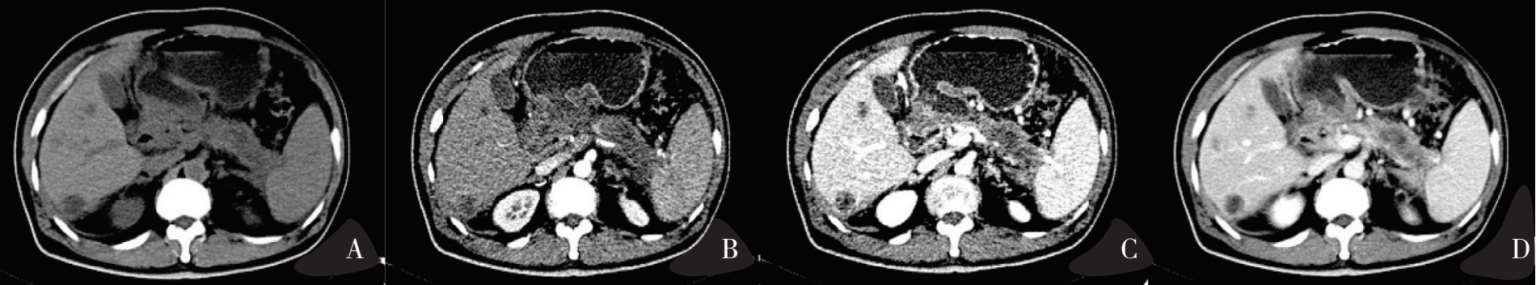

图8-1 正常胰腺CT平扫+三期增强扫描

图8-1A平扫期:胰腺密度与肝脏及脾脏相近,胰腺轮廓光滑,边界清楚,呈弯曲走行;图8-1B动脉期:胰腺实质明显强化,强化程度高于同层面肝实质,胰周动脉亦明显强化;图8-1C门脉期:胰腺实质仍维持明显强化,强化程度较同层面肝实质稍低,门静脉、脾静脉及肠系膜上静脉强化;图1d延迟期:胰腺实质强化程度下降,下腔静脉及肝静脉强化。